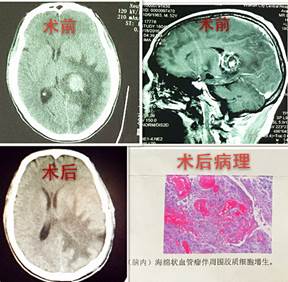

神外二病区成功切除脑深部海绵状血管瘤

近日,神经外科二病区在白西民主任医师的主持下完成了脑深部海绵状血管瘤切除术,患者已痊愈出院。

患者吕某,男,52岁,渭南华州区人,患者入院时自诉头痛12天,入院后行检查颅脑CT提示:左侧侧脑室后角占位,周围伴水肿。入院诊断为左侧侧脑室占位性病变。我市神经外科首席专家白西民主任医师高度重视,积极进行术前准备,在赵云洁住院医师的配合下在全麻下行左侧侧脑室肿瘤切除术,手术顺利。术后病理报告为:脑深部海绵状血管瘤伴胶质增生。患者术后头痛好转,无神经功能障碍。

脑内海绵状血管瘤也称海绵状血管畸形,或称海绵状瘤,多伴有癫痫、出血和局部神经功能缺损症状。此患者肿瘤位于侧脑室,位置较深,且毗邻重要结构,手术路径长,周围脑组织水肿广泛,颅内压高,手术难度较大,因此手术者必须具备扎实的神经外科解剖知识和熟练的显微外科技术。本例手术在神经外科二病区医务人员的努力下成功切除肿瘤,患者没有神经功能缺损,效果良好。